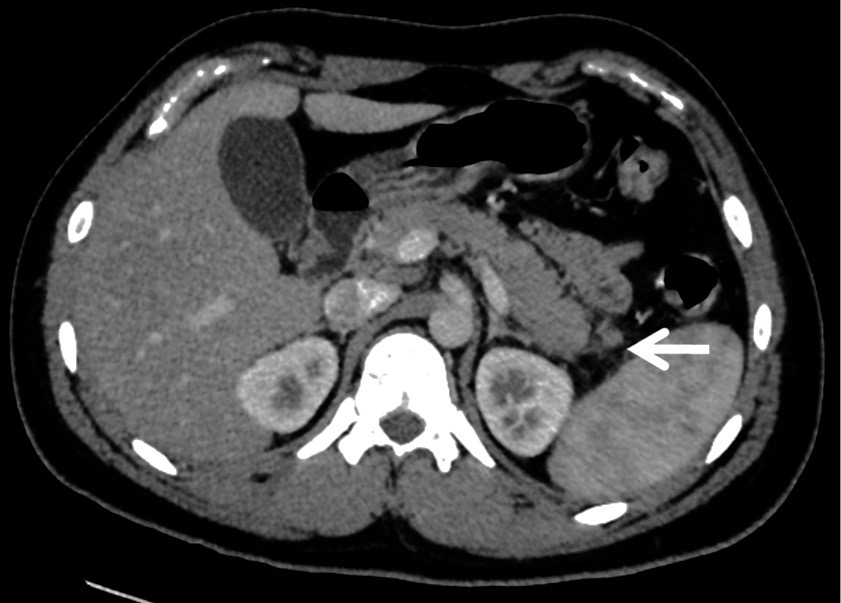

Given the patient’s history of repeated crisis possibly leading to organ dysfunction, computed tomography (CT) scans of the abdomen were ordered, which showed new fat stranding surrounding the pancreatic tail, representing peripancreatic inflammation (Figure).

Figure. Abdominal CT scan showing fat stranding surrounding the pancreatic tail.

Despite acute abdominal pain being a relatively common occurrence in patients with VOC, life-threatening complications can occur if the diagnosis of microvessel occlusion-induced pancreatitis is missed. Moreover, pancreatitis due to vaso-occlusion is clinically indistinguishable from other etiologies of acute abdominal pain from sickle cell VOC, and the initial diagnosis is based on clinical suspicion. Our patient met the criteria for acute pancreatitis with a serum lipase level elevated at greater than 3 times the upper limit, in association with the presence of epigastric pain radiating to the back and abdominal CT scans showing fat stranding surrounding the pancreatic tail.